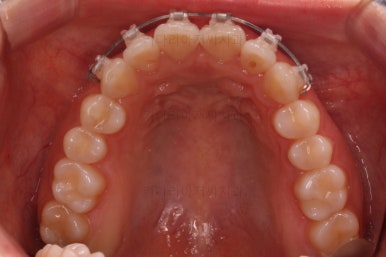

부산나비앞니교정 키다리아저씨치과에서 치료를 한 지 3개월째의 모습입니다.

굉장히 많이 가지런해 진 것을 볼 수 있어요.

그래도 여전히 나비앞니의 느낌이 남아있어서 미세한 조절을 더 하고 마무리를 하기로 했습니다.